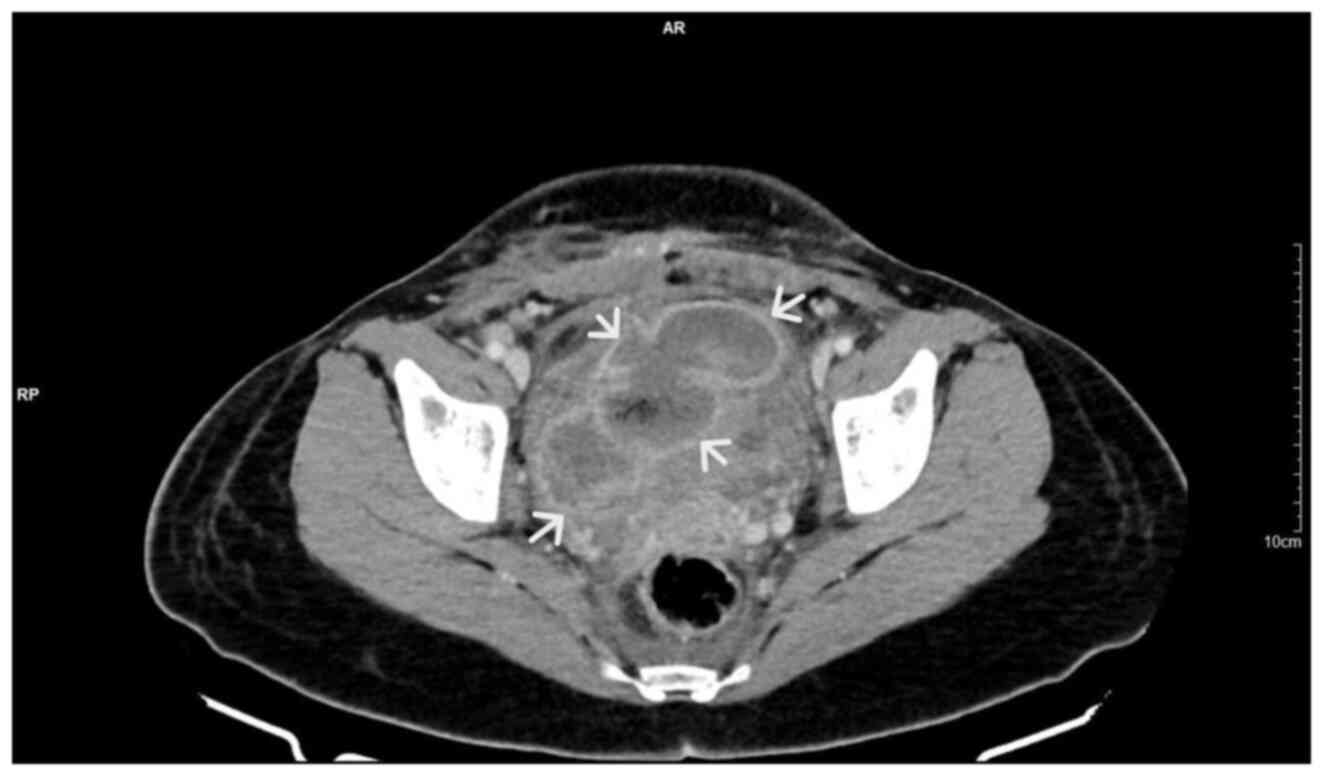

Large bladder flap haematoma following a caesarean section associated with right hydroureteronephrosis: A case report and a mini‑review of the literature

Post‑caesarean section bladder flap haematoma is a rare postpartum complication. There are currently no specific treatment protocols, at least to the best of our knowledge. In general, the failure of conservative treatment with antibiotics requires the re‑operation and surgical drainage of the haematoma. The present study describes the case of a primiparous pregnant woman who, at 40 weeks of pregnancy, delivered by caesarean section. On the 3rd post‑operative day, the puerperant, haemodynamically stable, developed febrile infection. During the evaluation, the presence of bladder flap haematoma associated with moderate right hydroureteronephrosis was found. The failure of conservative management led to the decision to perform a re‑laparotomy 1 week later. During the surgery, a large bladder flap haematoma was found with a retroperitoneal extension into the right parametrium. The surgical drainage of the haematoma and thorough haemostasis in the area of the vesicouterine pouch was performed. The patient was discharged from the clinic on the 5th post‑operative day following the re‑operation. After 2 weeks, an ultrasound revealed the complete repair of the lesions in the vesicouterine pouch and the right kidney. In the present study, a brief review of literature is also provided regarding the diagnostic and therapeutic management of patients with post‑caesarean section bladder flap hematoma.

Figure 1

Figure 2

Figure 3

Figure 4

Figure 5

Figure 6